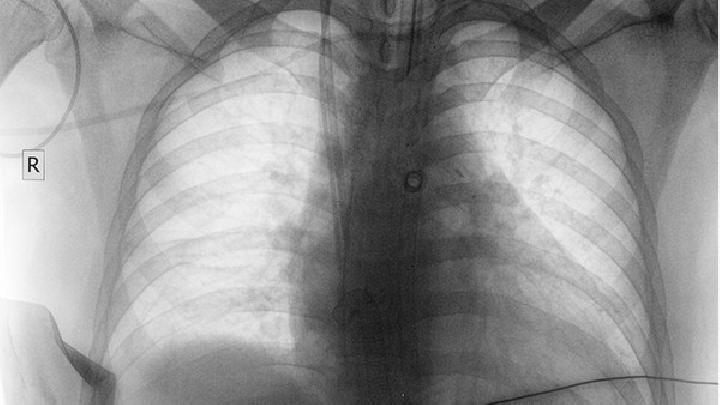

支气管肺癌属于临床上比较常见的肺部恶性肿瘤疾病,实际上这种疾病也属于肺癌的一种。支气管肺癌主要分为鳞癌、腺癌和小细胞肺癌。鳞癌和腺癌在支气管肺癌中占的比例很高,尤其现在患腺癌的人群不断增加,且女性居多。支气管肺癌治疗方式主要有手术、放疗、化疗以及靶向药物。

支气管肺癌是目前临床上最常见的肺癌之一,它属于临床上比较常见的肺部恶性肿瘤疾病。

这种病症自然是早诊断早治疗比较好。目前临床上将这种支气管肺癌分为鳞癌、腺癌和小细胞肺癌。而这三种支气管肺癌的治疗方法和方式都不尽相同。那么,具体都有哪些治疗方法呢?